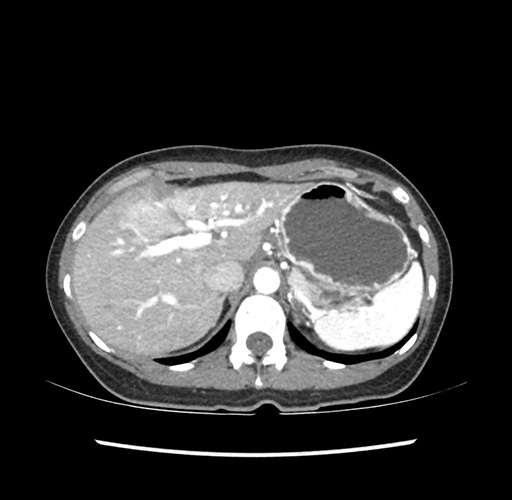

Imaging Analysis

Look through the patient's CT scan to identify any areas of concern for the necessary procedure.

Based on your CT findings, which issue(s) would give reason for "planned slowing down moment(s)" in this case?